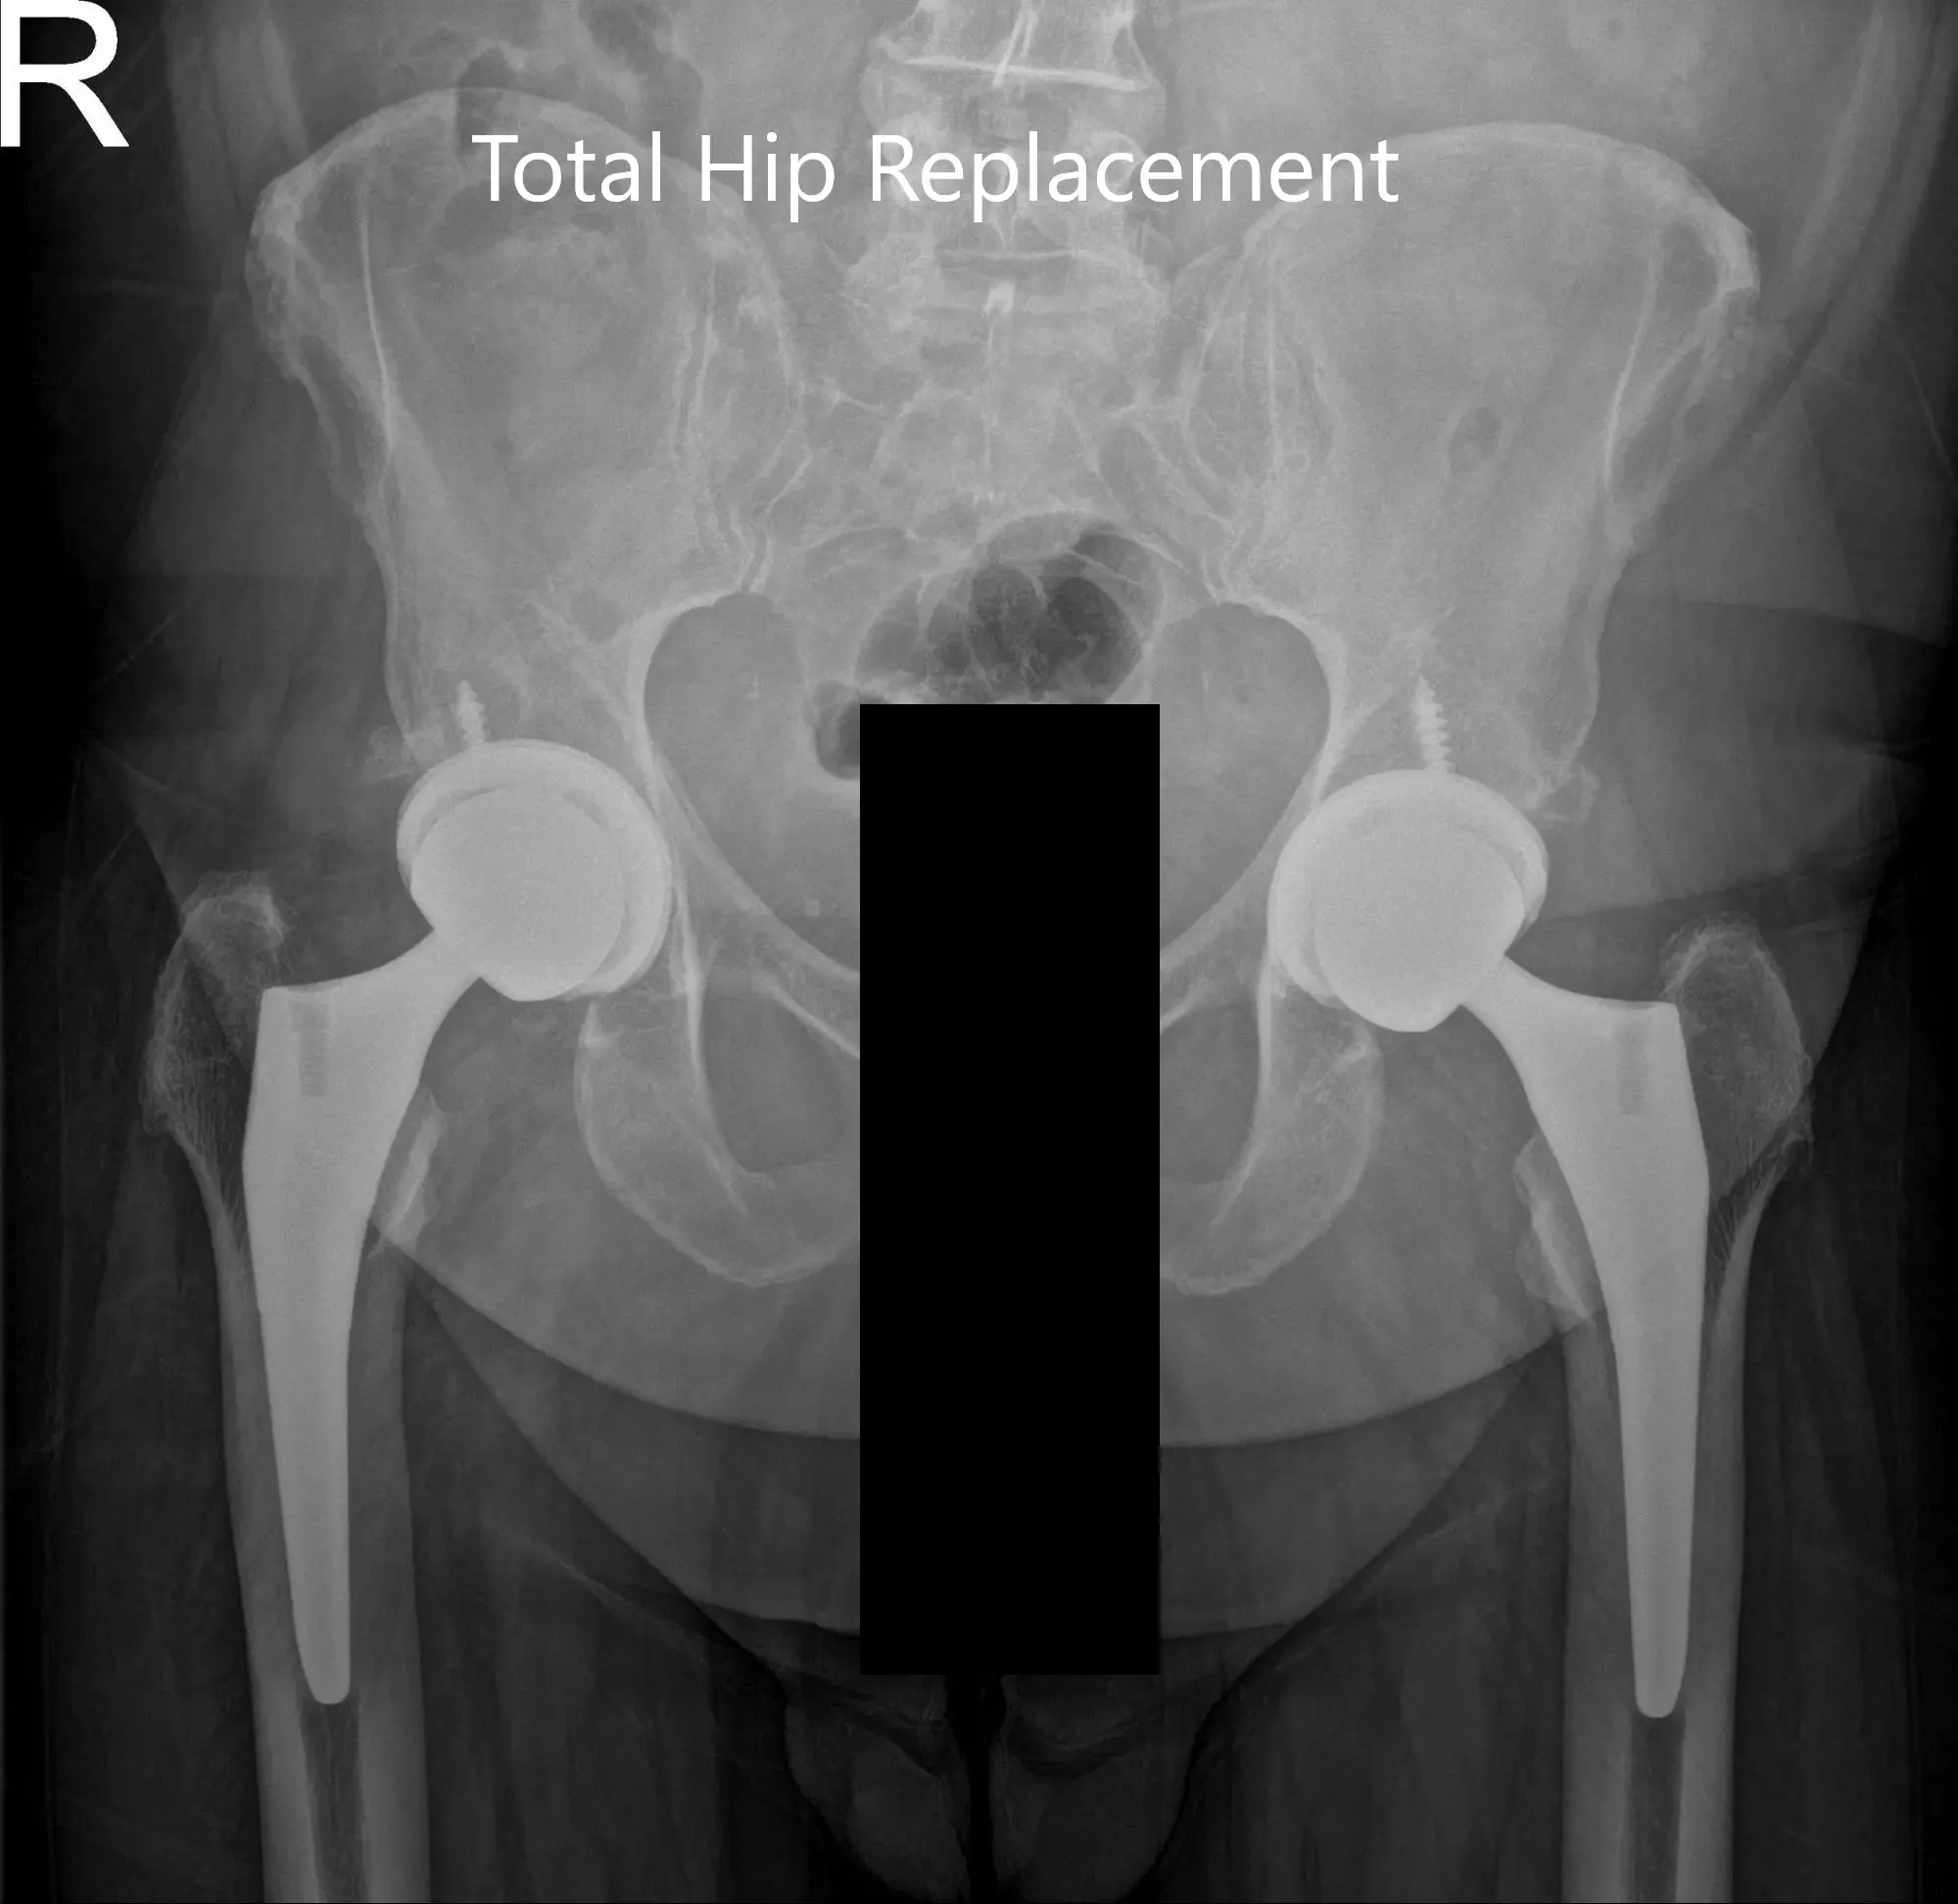

After the procedure, x-rays were obtained and were then saved to the PACS system. The alignment and stability on the x-ray was found to be acceptable. The patient was transferred to the postoperative care unit in stable condition.

Postoperative AP view of the Pelvis X-ray showing both hip joints with frog-leg lateral views of the right and left hip joints.